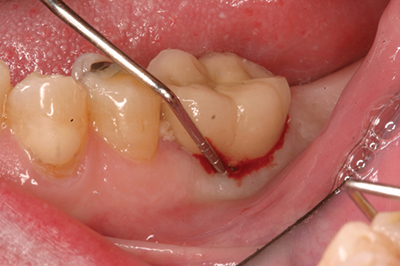

Late implant complications occur after the implant has integrated and the final prosthesis has been placed. Recognition of these complications via radiographic and clinical analysis is extremely important since many of these problems can be corrected if detected early. On the other hand, if allowed to progress, a minor complication can often result in loss of the implant and/or prosthesis. Late complications of the dental implant fall into the category of biologic or mechanical complications. Late biologic complications are those in which the peri-implant soft and hard tissues are affected. Peri-implant mucositis describes a reversible inflammatory reaction in the mucosa adjacent to an implant,(8) a term that has become known as implant gingivitis. Studies show that the prevalence of peri-implant mucositis can be as high as 50% to 80% of implants in function(9) with the etiology of peri-implant mucositis being bacterial plaque. Typical clinical presentation includes erythema, edema, swelling, and redness (Figs. 1 and 1a). Although bleeding upon probing and increased probing depths are not always indicative of peri-implant mucositis,(10) the absence of these two factors usually means implant health.(11)